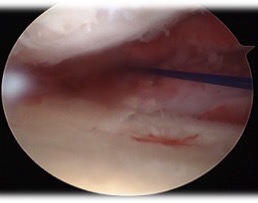

- mark site with needle

- just on inner margin of articular surface

- mark with shaver